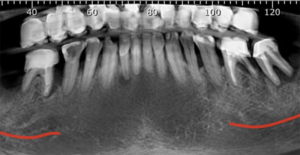

Figura 3 – Corte panorâmico de tomografia volumétrica do cone-bean. Observar o comprometimento da maioria dos elementos dentais inferiores.